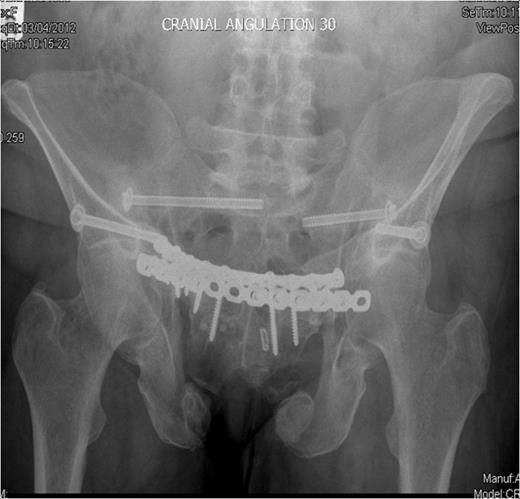

Inlet radiograph at 16 months post surgery demonstrating solid fixation and bony healing

Post-operative recovery was uneventful. Bone and soft tissue biopsies showed no abnormalities. She was kept non weight bearing for 12 weeks. Subsequent dual energy X-ray absorptiometry scanning revealed mild osteopenia for which she is being managed medically. She began full weight bearing at 3 months post surgery. Final follow-up at 16 months demonstrated that the fractures had healed, and the patient was pain free and mobilising unaided (Fig. 3 & 4).

Outlet radiographs at 16 months post surgery demonstrating solid fixation and bony healing